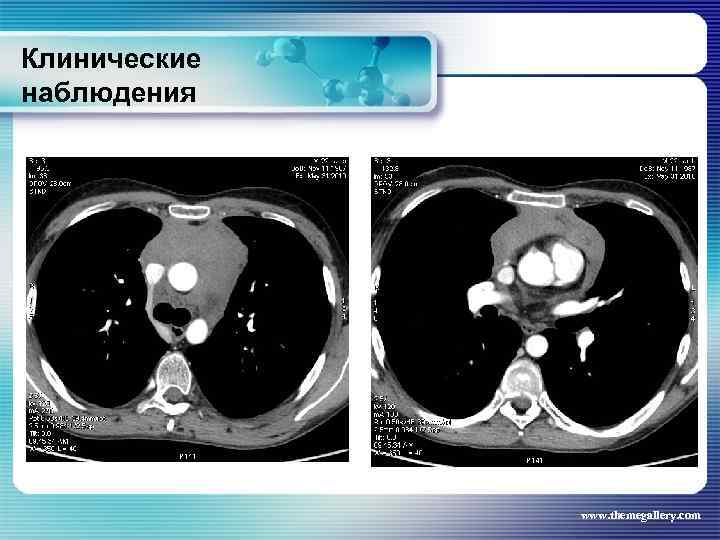

Клинические наблюдения Больной М. , 22 лет Заболел в январе 2010 года, когда появился мучительный кожный зуд, похудание, прогрессивный рост лимфатических узлов на шее, затрудненное дыхание. Самостоятельно обратился в поликлинику, направлен в гематологическое отделение. Выполнена биопсия шейного лимфатического узла: Лимфома Ходжкина. , нодулярный склероз Grade I. Уже отделении появилась лихорадка. При лабораторном обследовании выявлены признаки выраженной активности процесса. Результаты лучевого обследования: www. themegallery. com

Клинические наблюдения Больной М. , 22 лет Заболел в январе 2010 года, когда появился мучительный кожный зуд, похудание, прогрессивный рост лимфатических узлов на шее, затрудненное дыхание. Самостоятельно обратился в поликлинику, направлен в гематологическое отделение. Выполнена биопсия шейного лимфатического узла: Лимфома Ходжкина. , нодулярный склероз Grade I. Уже отделении появилась лихорадка. При лабораторном обследовании выявлены признаки выраженной активности процесса. Результаты лучевого обследования: www. themegallery. com

Клинические наблюдения Больной М. , 22 лет По результатам обследования сформулирован клинический диагноз: лимфома Ходжкина, нодулярный склероз, Grade I, III В стадия с поражением подчелюстных, шейных, надключичных лимфатических узлов с обеих сторон, подмышечных, переднегрудных, парастернальных, внутригрудных и абдоминальных лимфатических узлов, средостения. Было проведено 8 циклов BACOPP, на фоне лечения осложнение: полинейропатия рук, а затем асептический некроз головки правой бедренной кости. На фоне терапии отмечена положительная динамика как лабораторных данных, так и результатов лучевого обследования. Констатирована ремиссия www. themegallery. com

Клинические наблюдения Больной М. , 22 лет По результатам обследования сформулирован клинический диагноз: лимфома Ходжкина, нодулярный склероз, Grade I, III В стадия с поражением подчелюстных, шейных, надключичных лимфатических узлов с обеих сторон, подмышечных, переднегрудных, парастернальных, внутригрудных и абдоминальных лимфатических узлов, средостения. Было проведено 8 циклов BACOPP, на фоне лечения осложнение: полинейропатия рук, а затем асептический некроз головки правой бедренной кости. На фоне терапии отмечена положительная динамика как лабораторных данных, так и результатов лучевого обследования. Констатирована ремиссия www. themegallery. com

Клинические наблюдения Тот же пациент В сентябре-ноябре 2010 года выполнена телегамматерапия на шейные, надключичные лимфатические узлы, средостение (СОД – 36 Гр) и на аксилярную область (СОД – 24 Гр). Абдоминальные лимфатические узлы не облучали, т. к. они регрессировали на фоне ПХТ. Результаты лучевого обследования в настоящее время: www. themegallery. com

Клинические наблюдения Тот же пациент В сентябре-ноябре 2010 года выполнена телегамматерапия на шейные, надключичные лимфатические узлы, средостение (СОД – 36 Гр) и на аксилярную область (СОД – 24 Гр). Абдоминальные лимфатические узлы не облучали, т. к. они регрессировали на фоне ПХТ. Результаты лучевого обследования в настоящее время: www. themegallery. com